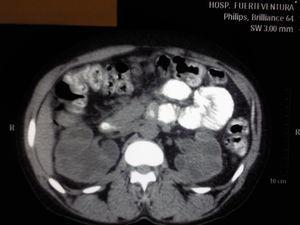

Presentamos el caso de una paciente mujer de 41 años de edad, sin antecedentes personales de interés que es remitida desde el servicio de urgencias por deterioro de función renal con creatinina sérica (Crs) 6.5 mg/dl, en el contexto de hemorragias vaginales con requerimientos transfusionales, siendo diagnosticada en ese momento por el servicio de ginecología de útero miomatoso. Se cursa ingreso para estudio, realizándose eco renal donde se objetiva una hidronefrosis bilateral grado IV con escasa diferenciación corticomedular sin objetivarse uréteres, por lo que se realiza tomografía axial computerizada (TAC) con el resultado de ureterohidronefrosis bilateral grado IV secundaria a compresión extrínseca por útero miomatoso de 13 x 9 cm (figura 1 y figura 2). Se avisa al servicio de urología, que implantan un catéter doble "J" en uréter derecho, con imposibilidad de colocación en uréter izquierdo. Se pide valoración por el servicio de ginecología, que postpone cirugía de histerectomía simple para una semana después. Tras realización de histerectomía, la paciente evoluciona desde el punto de vista clínico de forma favorable, no así desde el punto de vista bioquímico, manteniéndose Crs de 4.5 mg/dl tras 15 días postoperatorio. Se realizó nueva ecografía renal observándose hidronefrosis grado II y escasa diferenciación corticomedular, por lo que no se realizó biopsia renal percutánea, decidiéndose alta a domicilio con el diagnóstico de enfermedad renal crónica grado 4 secundaria a probable nefritis intersticial, para seguimiento en consulta de prediálisis.

Figura 1.